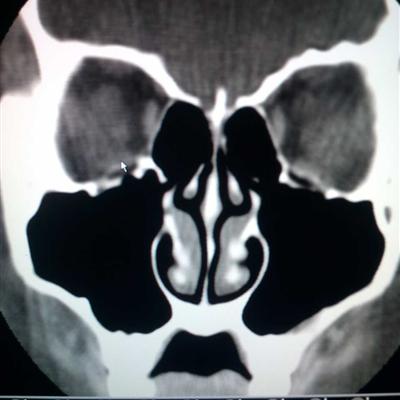

First of all, I just went to the hospital and was diagnosed with nasal cyst. The doctor asked my wife to have an X-ray examination. In the film, I could see the swelling of the nasal cavity, which was obviously the phenomenon of nasal cyst. Moreover, the doctor said that my wife's eyeball had been compressed and needed further treatment.